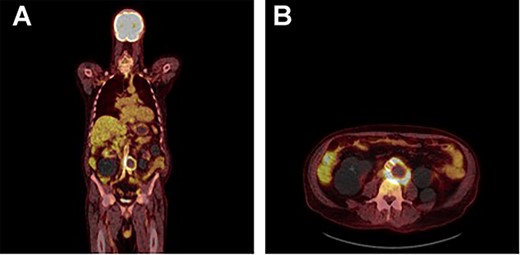

A 73-year-old male presented with a 1-week history of back pain on a background of hypertension, atrial fibrillation and bladder cancer. Computed tomography (CT) angiography demonstrated a 47 × 46 × 47 mm saccular aortic pseudoaneurysm of the infrarenal aorta with a contained rupture (Fig. 1). The patient remained hemodynamically stable with mildly elevated inflammatory markers (C-Reactive Protein (CRP), 85 mg/l, white cell count (WCC) 6.5 × 109/l). The abdominal aorta 5 months previously was normal on CT when a course of intra-vesical BCG for transitional cell carcinoma of the bladder had been ceased due to the development of fevers and syncope. Thus, Mycobacterium bovis involvement of the false aneurysm was suspected. Emergent endovascular repair was performed with a covered stent graft system successfully excluding the ruptured aneurysm sac on post-operative CT angiogram. A CT-guided fine needle aspirate of the aneurysmal sac was later conducted (Fig. 2). PCR of the aspirate returned a low-positive result confirming the diagnosis with M. bovis subsequently isolated on culture. Empirical antibiotics were ceased and he was commenced on a planned 18-month antituberculosis regimen of ethambutol, isoniazid and rifampicin guided by gene deletion analysis (GeneXpert MTB/RIF Ultra assay). Fluorodeoxyglucose-positron emission tomography (FDG-PET) scan was used to monitor the level of activity of the infection (Fig. 3). The patient was discharged home on Day 10 of admission. Aneurysm sac size was decreased at 3 and 6 months on CT angiogram and FDG-PET but there was ongoing FDG avidity around the aneurysm sac; there were no other sites of involvement. The patient remains otherwise well and has returned to his premorbid activities.

FDG PET/CT study demonstrating a rind of intense FDG uptake (SUV max 13.4) along the circumference of the lateral lower aortic aneurysm abutting the prosthesis however demonstrating no uptake tracking along the prosthesis. No other areas of FDG activity were demonstrated. (A) Coronal and (B) axial.